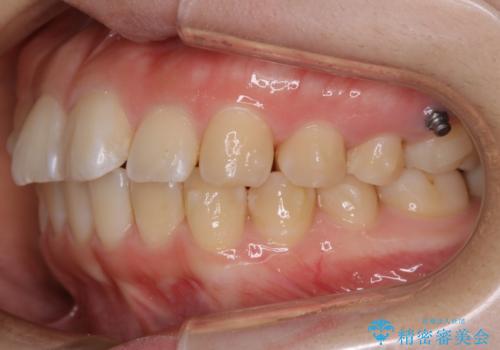

【非抜歯】ガタつきと歯軸を正して長持ちする歯へ

- 歯のガタつきと噛み合わせの改善を主訴に来院されました。

非抜歯で、少量の奥歯の移動と歯列の拡大・IPRを駆使して主訴を改善するための治療計画を立案しました。

マウスピースとマイクロインプラントを組み合わせることで、抜歯をしなくても歯並びを治すためのスペースを作ることができます。奥歯から順に移動させていくので前歯に変化が出るまでには時間がかかりますが、どの分健康な歯を抜歯することなく理想的な歯並びを手に入れることができます。